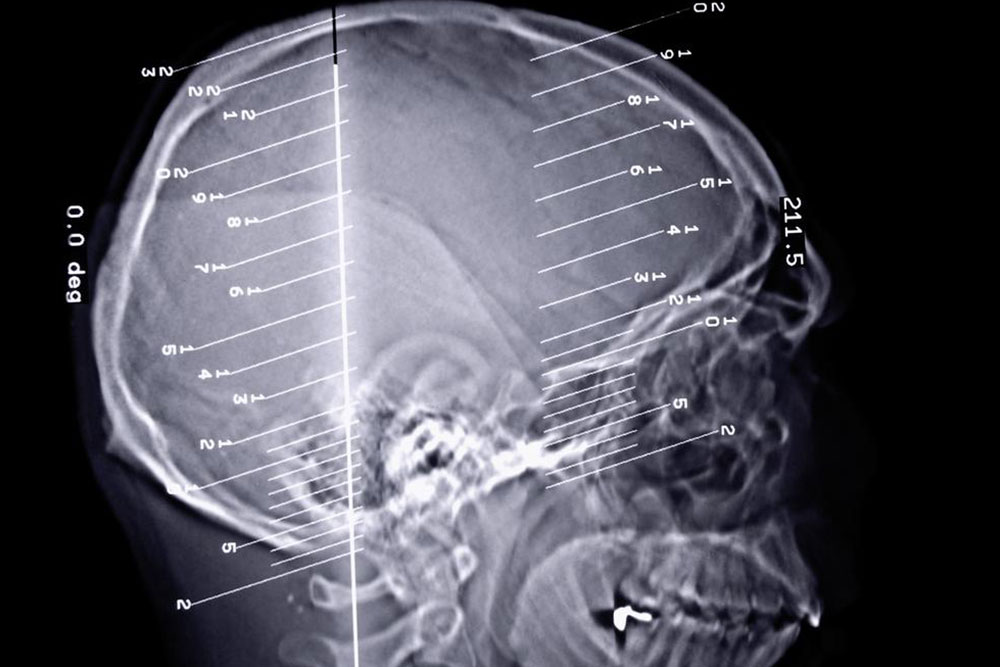

The human body can perform all its functions seamlessly when every organ of the body works in unison to perform the task. A slight change in the functions of the organ can disrupt the entire functioning of the body. Epilepsy seizures are a kind of disorder that occurs when we there is a problem in our brain’s electrical system.